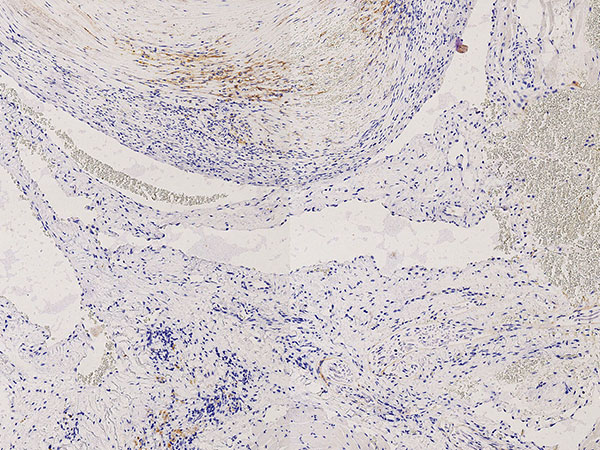

Histopathology, SMA stain ("smooth muscle actin"), 100x magnification: In this stain, the smooth musculature (smooth muscle actin; here smooth muscle cells of the vessel wall) is stained dark brown. This shows the highly irregular, asymmetric and in some cases even absent wall structure of the venous malformation. This is clearly dysplastic compared to a regular normal vein wall.